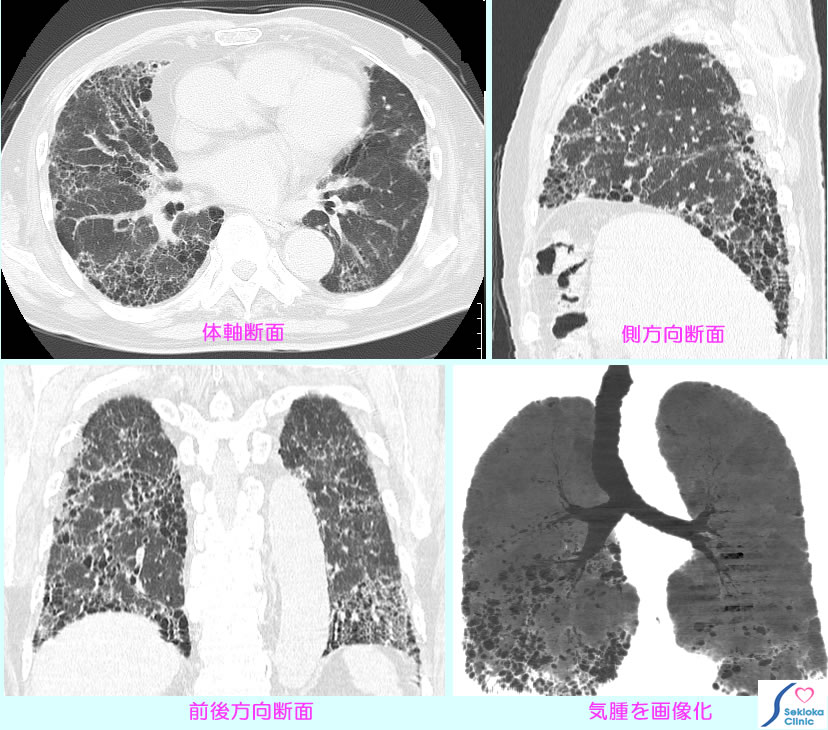

肺線維症 CT画像

原因となる間質肺炎急性期の精査には血液生化学検査、肺生檢も行われる。間質肺炎の活動状態の指標には血液生化学検査。肺機能や動脈血酸素飽和度の測定、運動負荷なども進行状況の評価に行われる。添付画像は蜘蛛の糸のごとく線維化した白い部分と黒く抜けた巣(気腫)の部分で蜂巣状と表現される。本例は運動時、動脈血酸素飽和度は90%(酸素分圧60mmHg)以下となり、息切れを生じる。携帯酸素を使用。